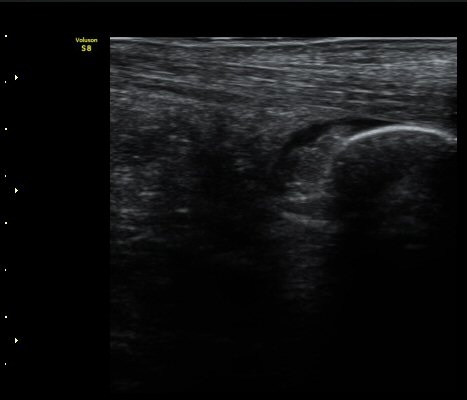

¼ö¾×Àú·ù°¡ °üÂûµÇ°í(±×¸² 1) °ÇÃø°ú ºñ±³Çϸé Â÷À̰¡ ¶Ñ·È´Ù´Ù(±×¸² 2).

ÁÖ»ç ÈÄ ÁÖ»ç¾×¿¡ ÀÇÇØ Á¡¾×³¶³» ¼ö¾×ÀÌ Áõ°¡µÈ °ÍÀÌ È®ÀÓ µÊ(±×¸² 3).